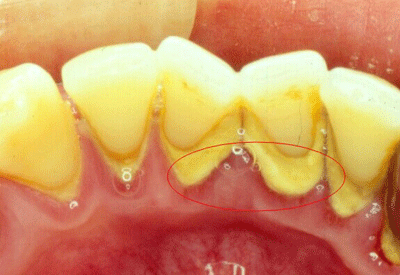

牙结石又称牙石,通常存在于唾液腺开口处的牙齿表面。牙结石开始是乳白色的软垢,会因逐渐的钙化而变硬。它是由75%的磷酸钙,15%~25%的水、有机物、磷酸锰、矿酸钙及微量的钾、钠、铁所构成。并呈现出黄色、棕色、或者黑色。牙结石是牙周病发展的一个重要致病因素。不注意养成良好的口腔卫生习惯,即使彻底洁治后,牙结石很容易很快再次沉积在牙齿表面。

牙结石对口腔来说是一种异物, 它会不断刺激牙周组织,并且会压迫牙龈,影响血液循环,造成牙周组织的病菌感染,引起牙龈发炎、萎缩, 形成牙周袋。当牙周袋形成后,更易使食物残渣、牙菌斑和牙结石在牙周袋部位堆积,,这种新的堆积又进一步破坏更深的牙周膜, 腐蚀和侵害牙槽骨,如此不断地恶性循环,终使牙周支持组织全部破坏殆尽,拔牙也成为选择。